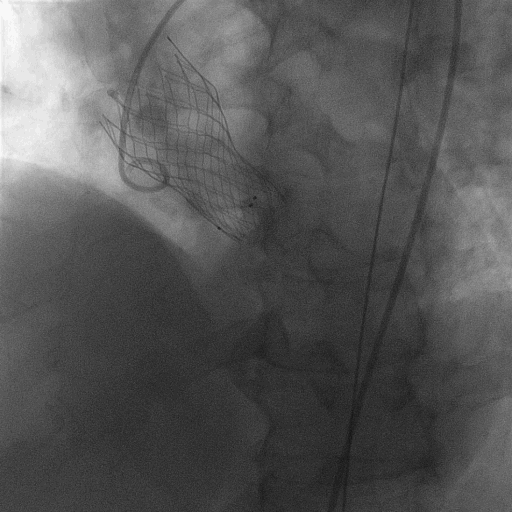

L23超高位释放

释放到2/3,观察瓣膜位置,与FEops评估一致,瓣膜发生了下滑

使用VenusA-Plus®回收功能以后,调整投射角度继续以高位释放